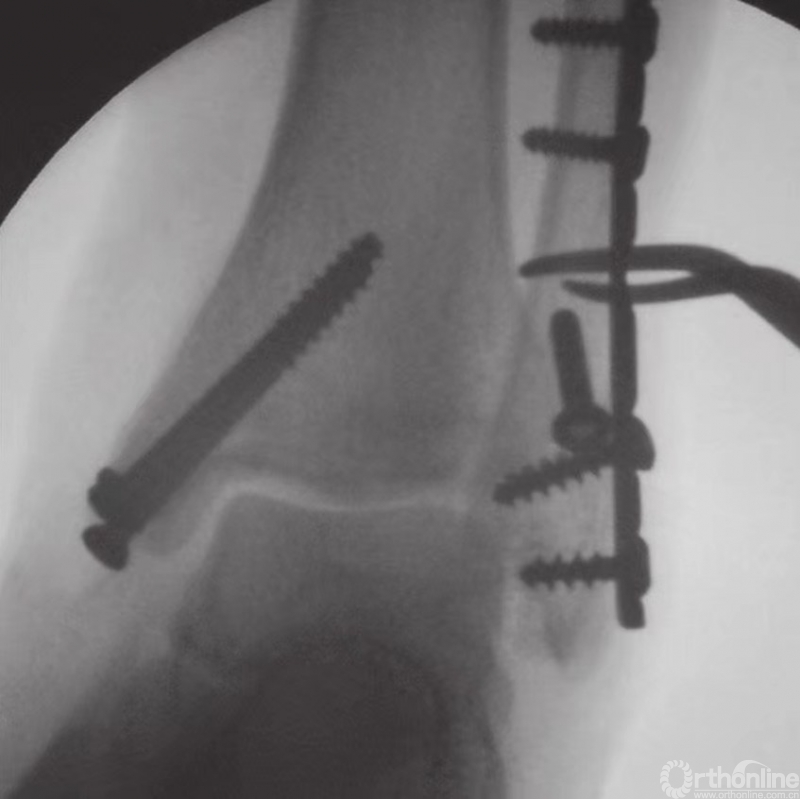

后踝固定技术

通过使用复位钳可完成经皮复位。将复位钳置于后外侧骨折片和前侧胫骨之上。在放置复位钳前,为避免腱和神经血管束的损伤,应进行充分剥离。在前侧胫骨开一个戳创的小切口后,将导丝从前向后穿过。固定时,通常自前向后放置4mm部分带螺纹的空心松质骨螺钉(图22)。

图22 自前向后置入螺钉固定后踝骨折

如果不能进行闭合复位,则经后外侧入路行切开复位。固定时,自后向前放置配有垫圈的4mm部分带螺纹的空心松质骨螺钉。如果骨折片在后内侧,则经后内侧入路进行复位,固定时螺钉从前向后放置。

下胫腓联合固定技术

在完成所有踝部骨折的固定之后,应评估下胫腓联合的稳定性。如果下胫腓联合关节上方或下胫腓联合水平发生腓骨骨折,应充分检查下胫腓联合的稳定性。在前后和中外两个平面上,应检查其完整性(图23)。另外,因为下胫腓联合发生损伤时腓骨可能向外旋转,故还应检查腓骨的旋转情况。

如果下胫腓联合不稳,则须进行固定,固定时采用皮质骨螺钉。由于腓骨在解剖关系上位于胫骨的后外侧,因此应将螺钉从后向前以30°的角度嵌入。一般认为,三皮质骨螺钉固定足以保证下胫腓联合的稳定性。螺钉应至少高过关节线2cm(图24和图25)。